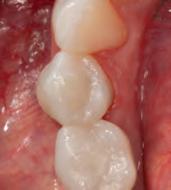

DISTO-OCCLUSAL CLINICAL CASE